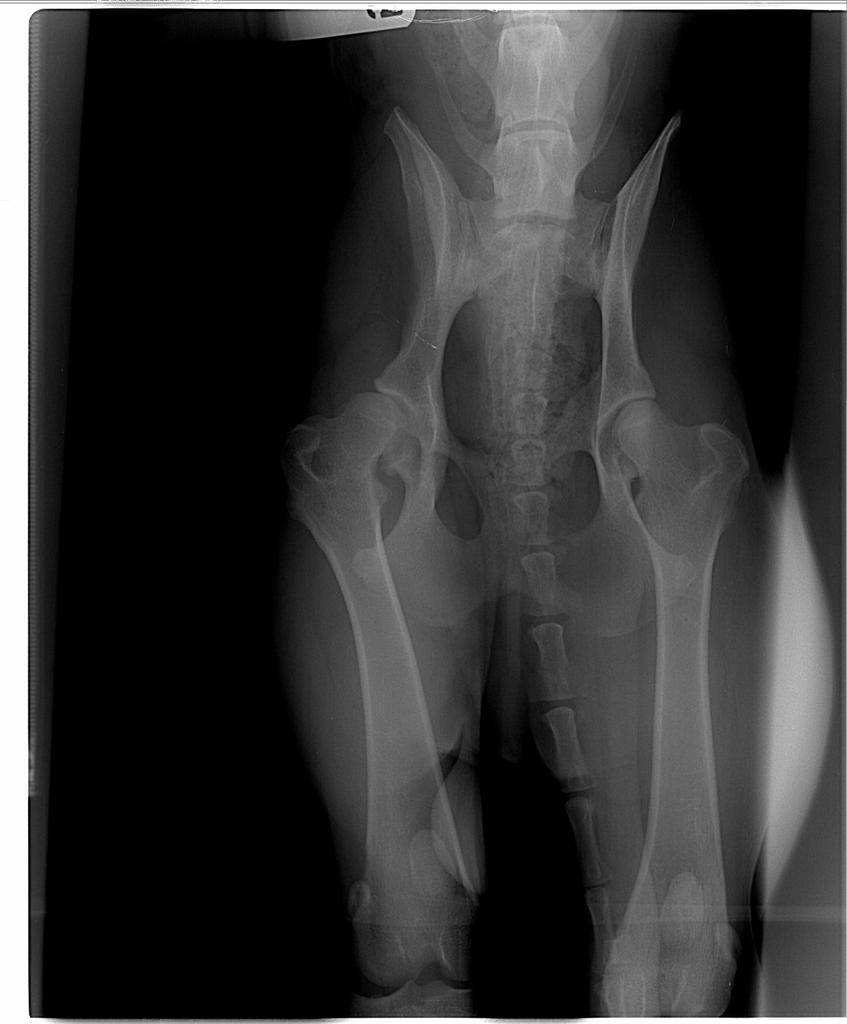

3. Podepne sie pod watek bo my niestety tez mamy dysplazje- a takie wielkie plany byly, mieszkam w UK importowalam psiaka bo brytyjska linia owczarkow niemieckich mnie nie ujela. Trenujemy do IPO, planowalismy British Seiger Show....niestety jestem przypadkiem, ktory potwierdza, ze nawet wspaniali rodzice, dziadkowie, pradziadkowie z biodrami normal, fast normal moga dac szczeniaka z dysplazja. Zbilansowane papu, suplement na stawy, bez szalenstw z psami czy skokami .....Spojrzcie tylko na rtg- zalamana jestem. Nie wiem czy udalo mi sie zalaczyc zdjecia...